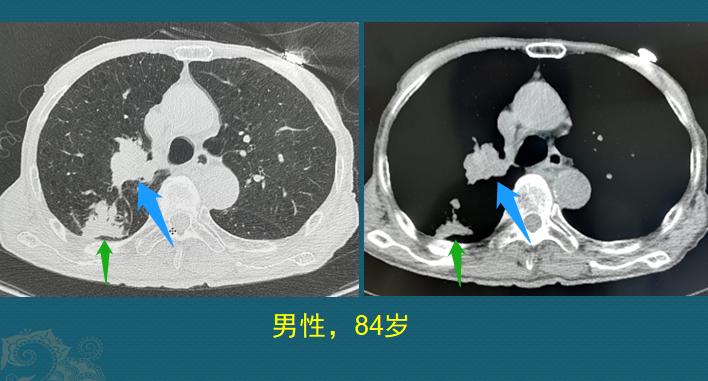

病例3,男性,84岁

这位老爷子是咳嗽、发热、不爱吃饭住院,CT发现右上肺门肿瘤(蓝箭头),伴有阻塞性肺炎(绿箭头):

老人是因为肿瘤阻塞支气管,引起远侧肺组织阻塞性炎症,发烧、咳嗽才发现的。